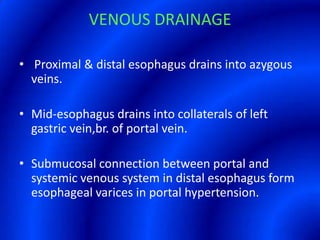

This document provides information about a barium swallow procedure. It begins with an introduction and overview of the embryology and anatomy of the pharynx and esophagus. It then describes the procedure itself, including preparation, technique, views obtained, and indications. Specific conditions that may be examined include pharyngeal and esophageal webs, foreign body impaction, scleroderma, dysphagia, mediastinal masses, and carcinoma. Diagrams are provided to illustrate normal anatomy and various pathological findings.